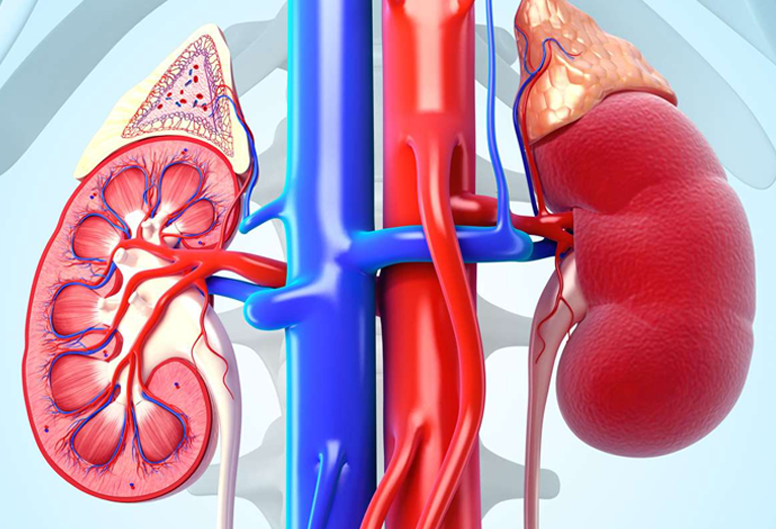

Dr Sushrut Fuladi is a well-known Consultant Nephrologist and Renal Transplant Physician with

expertise in treating patients of Acute Kidney Injury, Chronic Kidney Disease, Hypertension and

Diabetes related renal disorders, and renal replacement therapies.